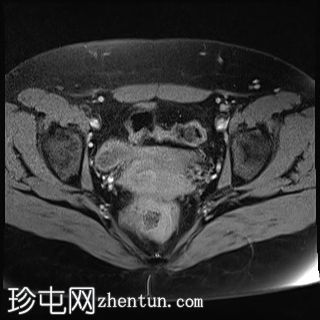

轴位

T2加权像

双侧卵巢位置接近(卵巢相吻),左侧卵巢内可见一边界清晰的囊性病变,大小约3.1 × 2.7 × 2.9 cm,T1加权像呈高信号,T2加权像可见暗点征及内部暗点征。以上MRI特征符合卵巢子宫内膜异位囊肿的诊断。

右侧卵巢可见一囊肿,大小约为 2.8 × 2.0 × 2.2 cm,T1 加权像呈高信号,囊内可见液-液平面,提示囊内含有不同时期的出血性物质。由于对侧卵巢存在典型的子宫内膜异位囊肿,且该囊肿无强化,影像学表现强烈提示为另一子宫内膜异位囊肿。

双侧卵巢均可见多个小卵泡。